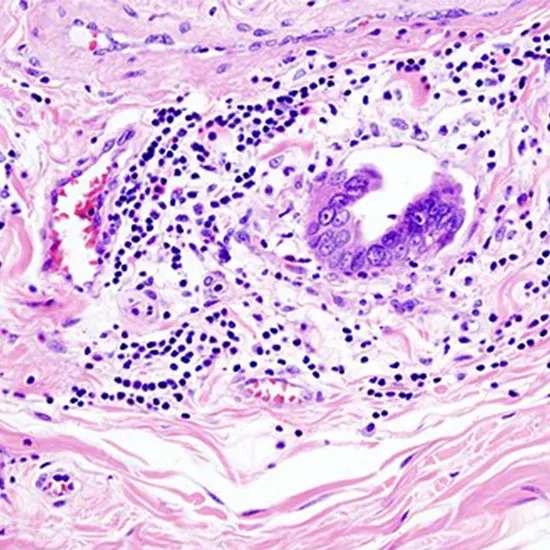

Adenocarcinoma : This is the most common type of gallbladder cancer and begins in the cells of glandular that line the inside of the gallbladder. It accounts for about 90% of cases.

Biopsy : A biopsy involves the removal of a small sample of tissue from the gallbladder for examination under a microscope. This test can help confirm the presence of cancer cells in the gallbladder.